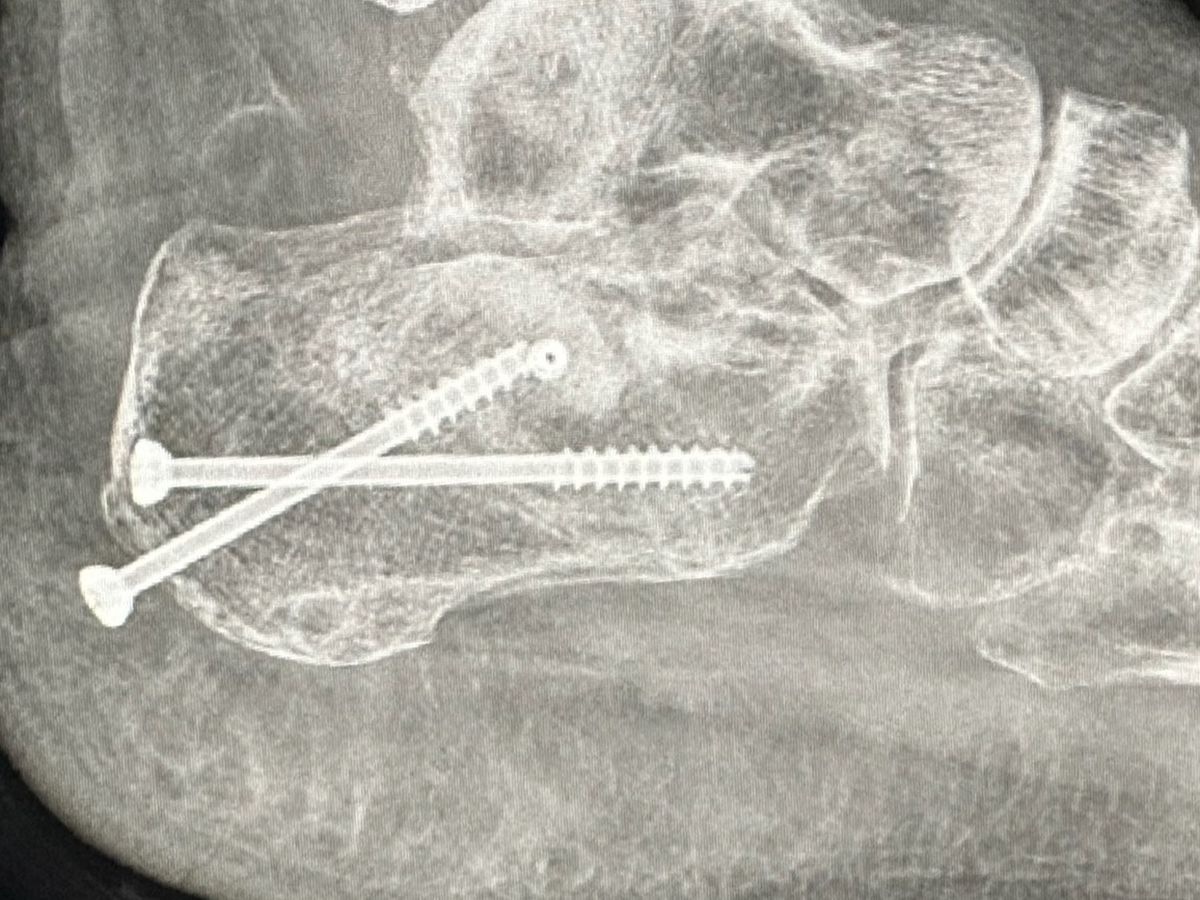

she's been working hard all her life but unfortunately a year and a half she had this unfortunately accident that she broke her heel bone in pieces she was ready to buy her dream house right before this accident happened now she spent all her savings in this situation and now she needs another surgery because the screws are coming out and she can potentially get the bone infected and high risk to get her foot amputate . . she cannot get social security and not disability because she worked with 1099 .. she needs help to keep up with rent and bills and she's terrified to get evicted most because she have two puppies that she needs to protect , and Plus she's been dealing with depression , she's in a good attitude and hope , from my heart thank you. Alma